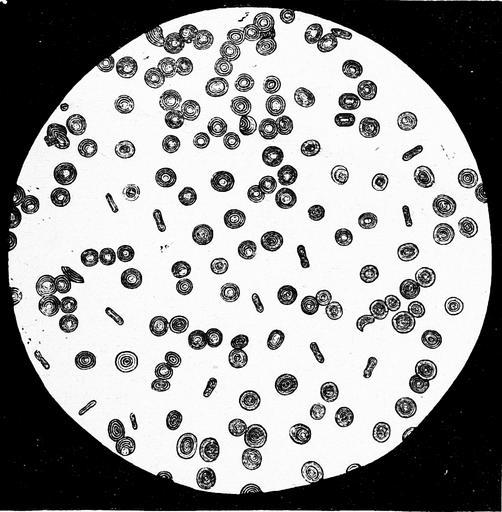

MAKE A MEME View Large Image Die Gartenlaube (1876) b 697 2.jpg 697 698 Images from Gartenlaube requiring categorisation

View Original:Die_Gartenlaube_(1876)_b_697_2.jpg (975x995)